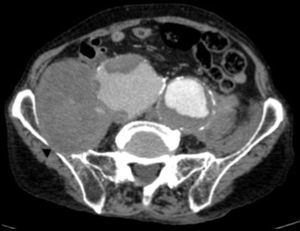

Paciente varón de 86 años, hipertenso en tratamiento con 2 fármacos, con historia de dolor lumbar con irradiación crural derecha de varios meses de evolución que se había controlado parcialmente con tratamiento sintomático. Su reumatólogo le había prescrito RM dorsolumbar que no llegó a realizarse ya que el paciente acudió antes a urgencias por aumento de la intensidad del dolor. En la analítica, hemoglobina 8,4g/dl, LDH 318 U/l, creatinina 1,29mg/dl, PCR 6,16mg/dl, VSG 24mm/h y leve hipoproteinemia. Ausencia de signos de inestabilidad hemodinámica. Se realizó una TC abdominopélvica con contraste por vía intravenosa que muestra aneurismas ilíacos aislados bilaterales>6cm (fig. 1) con rotura contenida del derecho (fig. 2), que desplazaba el músculo psoas (fig. 3) y horadaba el hueso ilíaco ipsolateral (fig. 4). El paciente es sometido a by-pass aortobifemoral pero lamentablemente fallece en el postoperatorio.

Los aneurismas ilíacos aislados, sin aneurisma aórtico asociado, son raros1. Son relativamente difíciles de identificar, ya que hasta un 40% de ellos se pueden presentar con rotura2. La tasa de incidencia de causas extraespinales de ciática es baja3. Igualmente, el aneurisma roto crónico constituye una entidad peculiar. Todas estas circunstancias se aúnan para que el diagnóstico, la mayoría de las veces, sea erróneo y tardío4. Suele tratarse de una rotura laterodorsal hacia las inserciones anteriores del psoas que contiene el hematoma, evitando la extravasación masiva pero no la infiltración de las raíces del plexo lumbosacro, lo que origina un dolor crónico lumbar con irradiación al miembro inferior5, siendo esta su presentación más frecuente6. El diagnóstico puede realizarse con TC abdominal7, pudiendo también visualizarse en la RM lumbar (corte parasagital)7,8. En cualquier momento de la evolución, el aneurisma puede sufrir una rotura aguda secundaria4. Este caso sirve para recordarnos, en nuestra práctica diaria, que la causa aneurismática puede estar implicada en los síntomas de ciática9.